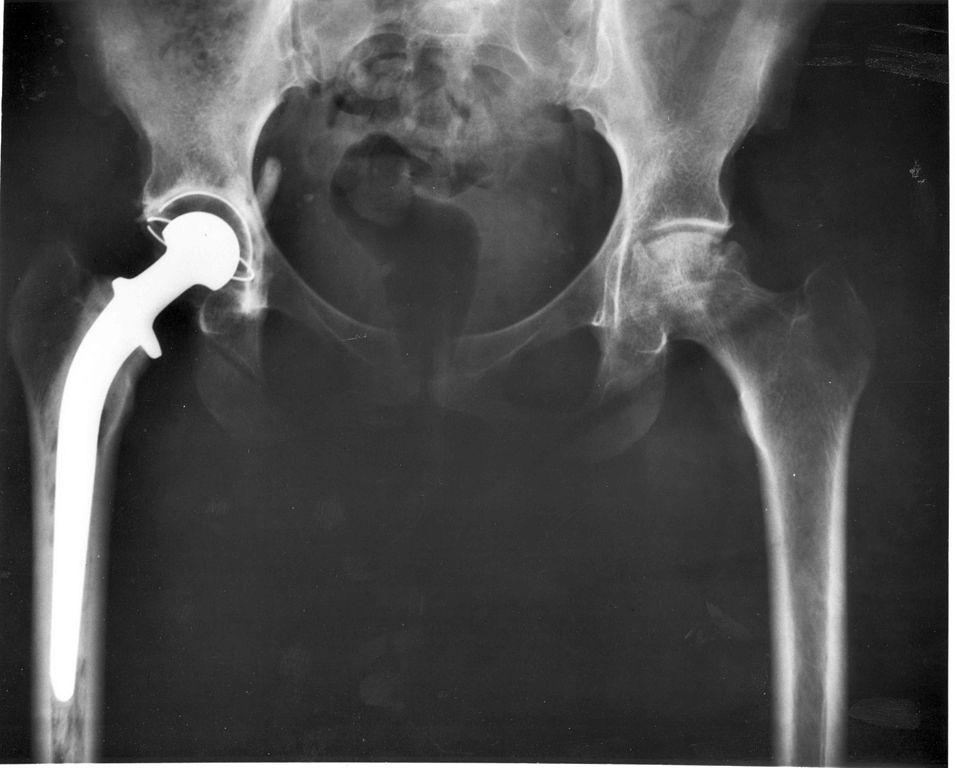

All Posts November 26, 2014 | No Comments Mercy Memorial Hospital System Announces Direct Anterior Approach to Hip Replacement